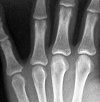

Рентгенография кисти

Рентген кисти. Методы лучевой терапии применяют при подозрении на перелом и вывих пястной кости, аномальное развитие кисти, дегенеративно-дистрофические и воспалительные процессы различной этиологии, злокачественные новообразования и доброкачественные кости кисти. Исследование проводится без специальной подготовки. Две или три проекции используются для оценки состояния костей и суставов кисти. На изображениях показаны метакарпы, пястно-фаланговые суставы и кости карпа. Из-за высокой радиационной нагрузки использование этой техники не рекомендуется в детстве или во время беременности.

Рентгенография костей кисти при травме назначается при подозрении на перелом и вывих пястной кости. В ортопедии исследование используется для пороков развития и остеоартрита различного происхождения, в онкологии - для опухолевых поражений, в ревматологии - для заболеваний, связанных с поражением мелких суставов кисти. В гнойной хирургии процедура применяется при артрите, распространении гнойного процесса на кости кисти при инфицированных ранах, панариции, флегмоне кисти.